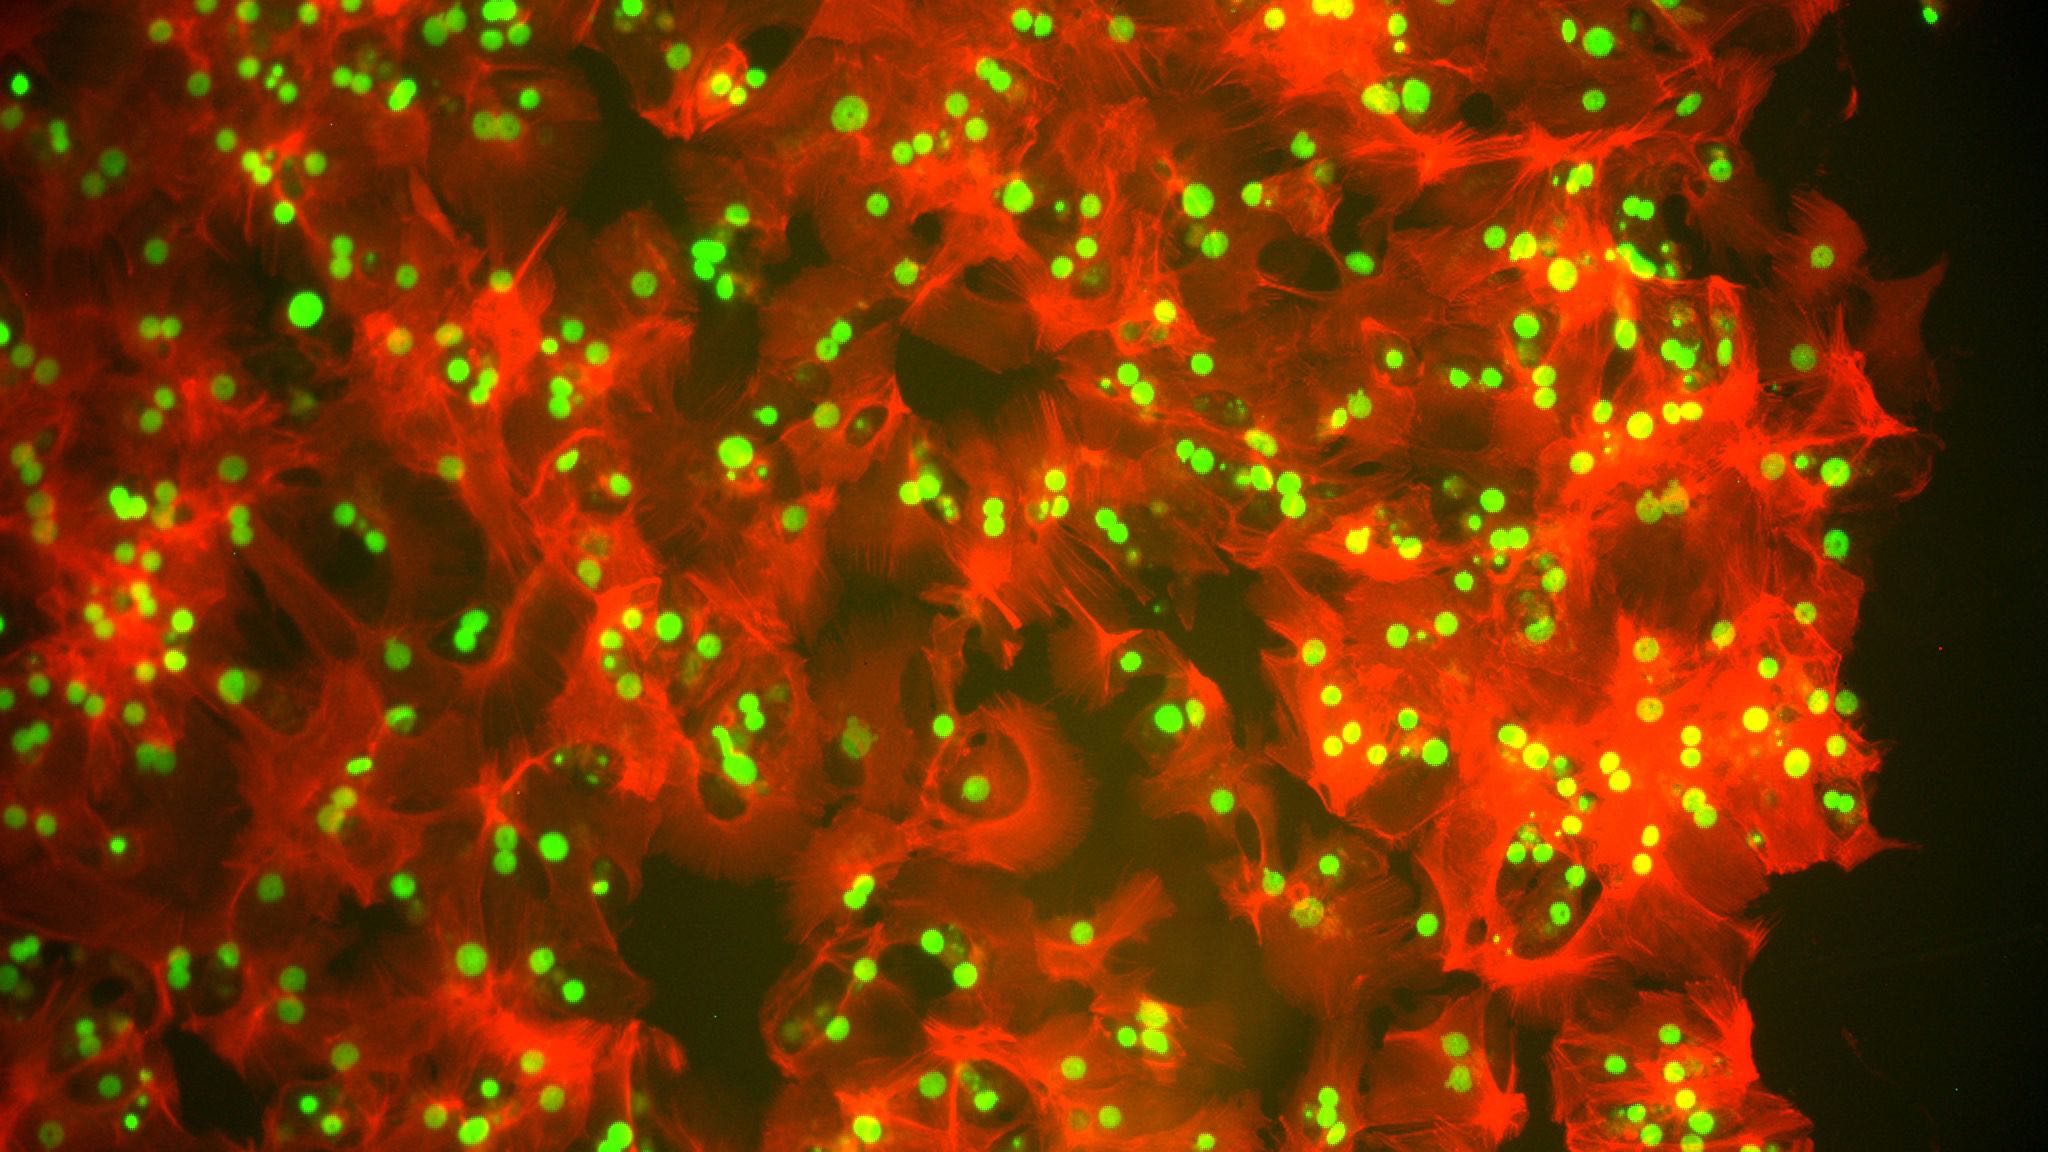

miRNA & the Liver

Regenerative Medicine denotes the process of creating living, functional tissues to repair or replace tissue or organ function lost due to age, disease, damage, or congenital defects. Other concepts are based on the application of hybrid organs and processed and modified cells. Therefore, this interdisciplinary research field combines the methods of clinical medicine with molecular and cell biology, biochemistry, as well as materials sciences, medical engineering and nanotechnology.